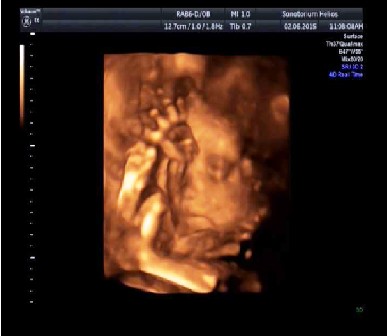

Byla jsem na 4D ultrazvuku

V úterý jsem zavítala v doprovodu mé maminky na 4D ultrazvuk do Helios studia. Malá se bránila zuby nehty, aby se hezky ukázala. Jak je normálně přes den v klidu, tak s sebou mlela a schovávala se za ručky, jak mohla, asi se jí očividně moc ultrazvuk nelíbil, ale co zmohla. Odnesla jsem si moc pěkné video a fotky. Paní doktorka z Helios centra mi vše ukázala a vysvětlila na 4D, kolik má malá gramů, jak pěkně roste apod. A další den pravidelná měsíční prohlídka u mé paní doktorky, proběhla rychle, jenom se mrkla, zda je vše v pořádku a šla jsem domů. Malá moc pěkně roste, z 330 g má už 620 g.

Silvi - krásné fotečky z ultazvuku.